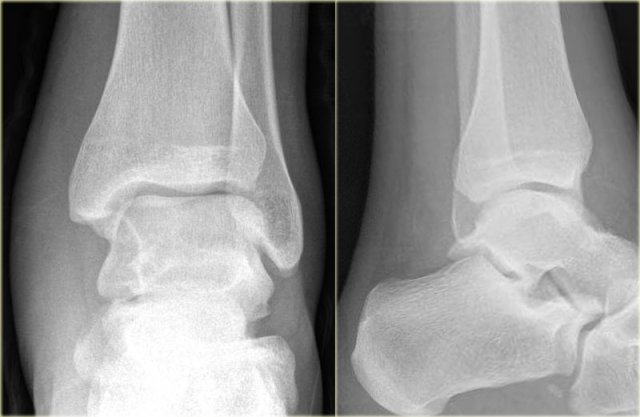

Triplane fracture Triplane fracture

At first this looks like a Weber B fracture with an oblique fracture in the fibula as seen on the lateral view (black arrows).

Notice however that this fracture line stops at the level of the epiphyseal plate.

So this is the fracture of the metaphysis in the coronal plane.

On the AP-view there is a lucency within the epiphysis, which is the epiphyseal fracture in the sagittal plane.

Notice also that the medial epiphysis is already closed, while the lateral portion is still open(blue arrows).

We have to assume that there is an epiphysiolysis of this lateral portion.

Here another example.

There is only a small metaphyseal fragment, which is usually the case (red arrow).

The fracture through the epiphysis is indicated by the blue arrow.